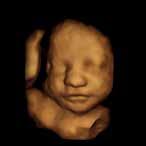

Local, Piper Richie

When Suha Dabit first heard the words “Hypoplastic Right Heart Syndrome” during a routine ultrasound, her world stopped. Her unborn daughter, Nadia, was missing half of her heart—a diagnosis that carried a lifetime of uncertainty, countless surgeries, and fragile hope. In that moment, Suha didn’t yet know how deeply her family’s journey would reshape not only their lives but also the lives of countless others across the world.

The early months of Nadia’s life were spent in and out of the hospital. At just five days old, she had her first openheart surgery. Two more followed before her third birthday. Though Nadia was declared a surgical success, her tiny heart couldn’t keep up. Six weeks after her third procedure, her parents were told she needed a heart transplant. With unimaginable strength, they agreed to a complex and rare intervention: implanting a Berlin Heart—a pediatric ventricular assist device that would keep Nadia alive until a donor heart became available.

Hooked up to machines for nearly six months in intensive care, Nadia refused to let her circumstances dim her light. She played games with nurses, handed out stickers, sang songs down the hallway, and brought joy to everyone who crossed her path. Her spirit was magnetic, unbreakable, and unforgettable. Finally, a donor heart arrived—offering a second chance, a new rhythm, and a new chapter. But for Suha, Nadia’s healing wasn’t the end of the story—it was the beginning of a mission.

During those long hospital days, Suha saw parents grappling with heartbreak and hope, often without the time or means to capture precious moments with their children. She watched families whisper goodbye with only a few blurry phone photos to hold onto. That loss— the absence of tangible memories— stuck with her. She knew there had to be

a way to honor these stories with beauty, dignity, and permanence.

That desire became World of Broken Hearts, a nonprofit born from a mother’s pain and transformed into a platform of healing and connection. Suha picked up a camera—an entry-level Canon Rebel— and taught herself photography. What started as a few portraits gifted to families at the same hospital where Nadia was treated, grew into something much bigger. In 2015, she launched World of Broken Hearts officially, and by 2018, it became a 501(c)(3) nonprofit. Through the organization, Suha offers free professional portrait sessions for families of children with congenital heart defects. Whether in the NICU, at home, or following surgery, each photograph captures more than a moment—it preserves courage, love, and legacy. Some children survive and thrive. Others don’t. But every family is left with images they’ll treasure for a lifetime.